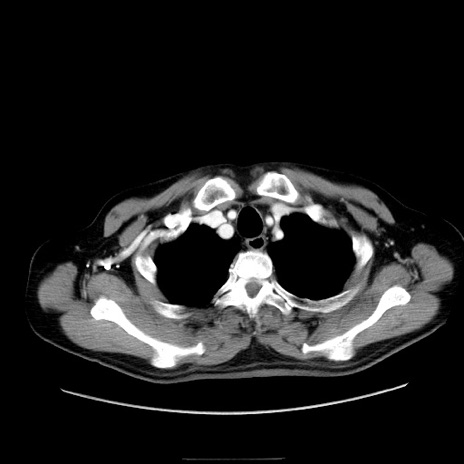

症例30(横断像)

【症例】80歳代男性

【主訴】臍周囲痛

【現病歴】約6時間前から臍下部痛が出現。次第に腹部膨隆・背部痛も生じてきたため来院。背部痛の場所は変化しない。

【身体所見】意識清明、BT 36.3℃、BP  131/87mmHg、P 87bpm、SpO2 100%(RA)、臍周囲自発痛・圧痛あり、反跳痛なし、自発痛部位に一致して板状硬あり、腹部膨隆、腸雑音減弱、CVA tenderness両側陰性。